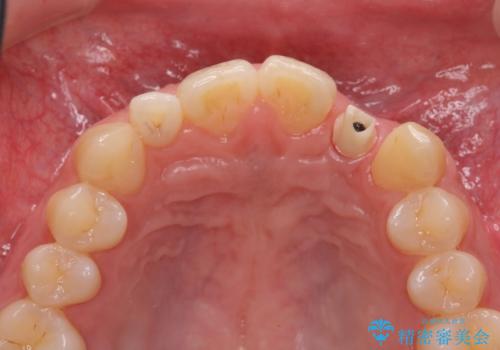

前歯部 インプラント治療

- 前歯の永久歯が元々なく、乳歯を失ったタイミングで前歯の審美性の回復を求めて来院されました。

機能・審美性の回復手段として、インプラント治療・ブリッジ・部分床義歯が考えられます。

それぞれの治療に特徴がありますが、取り外しの必要がなく隣の歯を削る必要も必要ないインプラント治療を選択されました。

前歯部にインプラントを埋入し、きれいに仕上げるためには骨の造成技術や歯肉の厚みを増すような処置を行い、インプラント周囲の環境を整備することが肝要です。